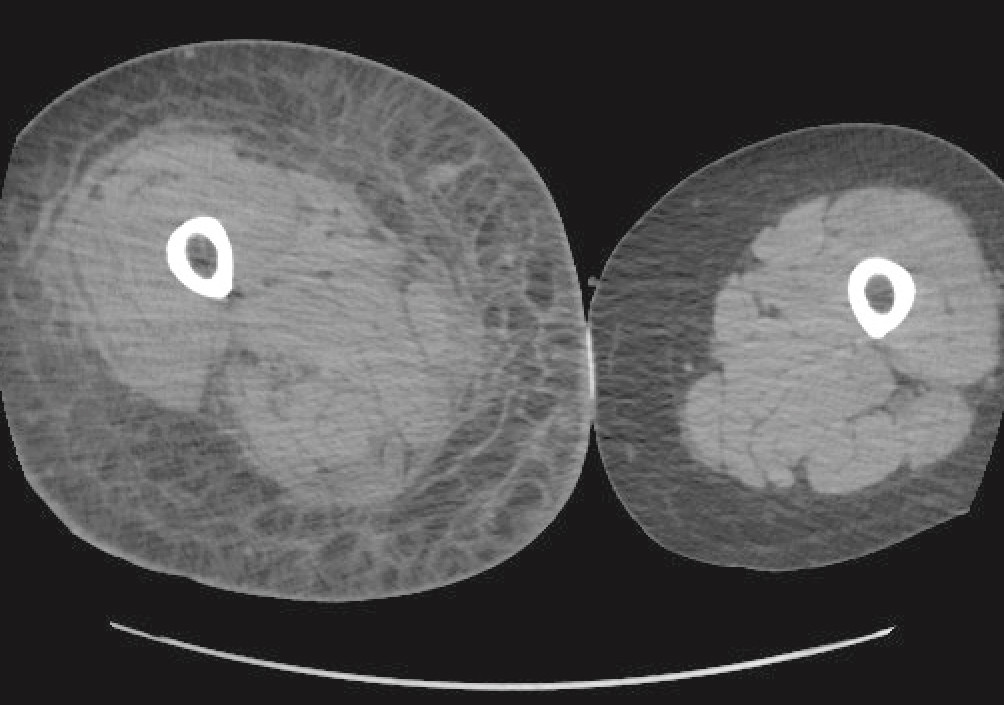

CT of the right lower extremity showed severe subcutaneous oedema, involving deeper structures such as the muscle and fascia (Figure 1). CT of the thorax and abdomen revealed phlegmon of the musculature of the abdominal wall. There were no radiological signs of gas production in deeper tissues. CT findings were consistent with a deep soft tissue infection, such as necrotising fasciitis. After a total of five days at the local hospital, the patient was transferred to the nearest central hospital with expertise in plastic surgery.

Figure 1 CT of lower extremity with subcutaneous oedema.